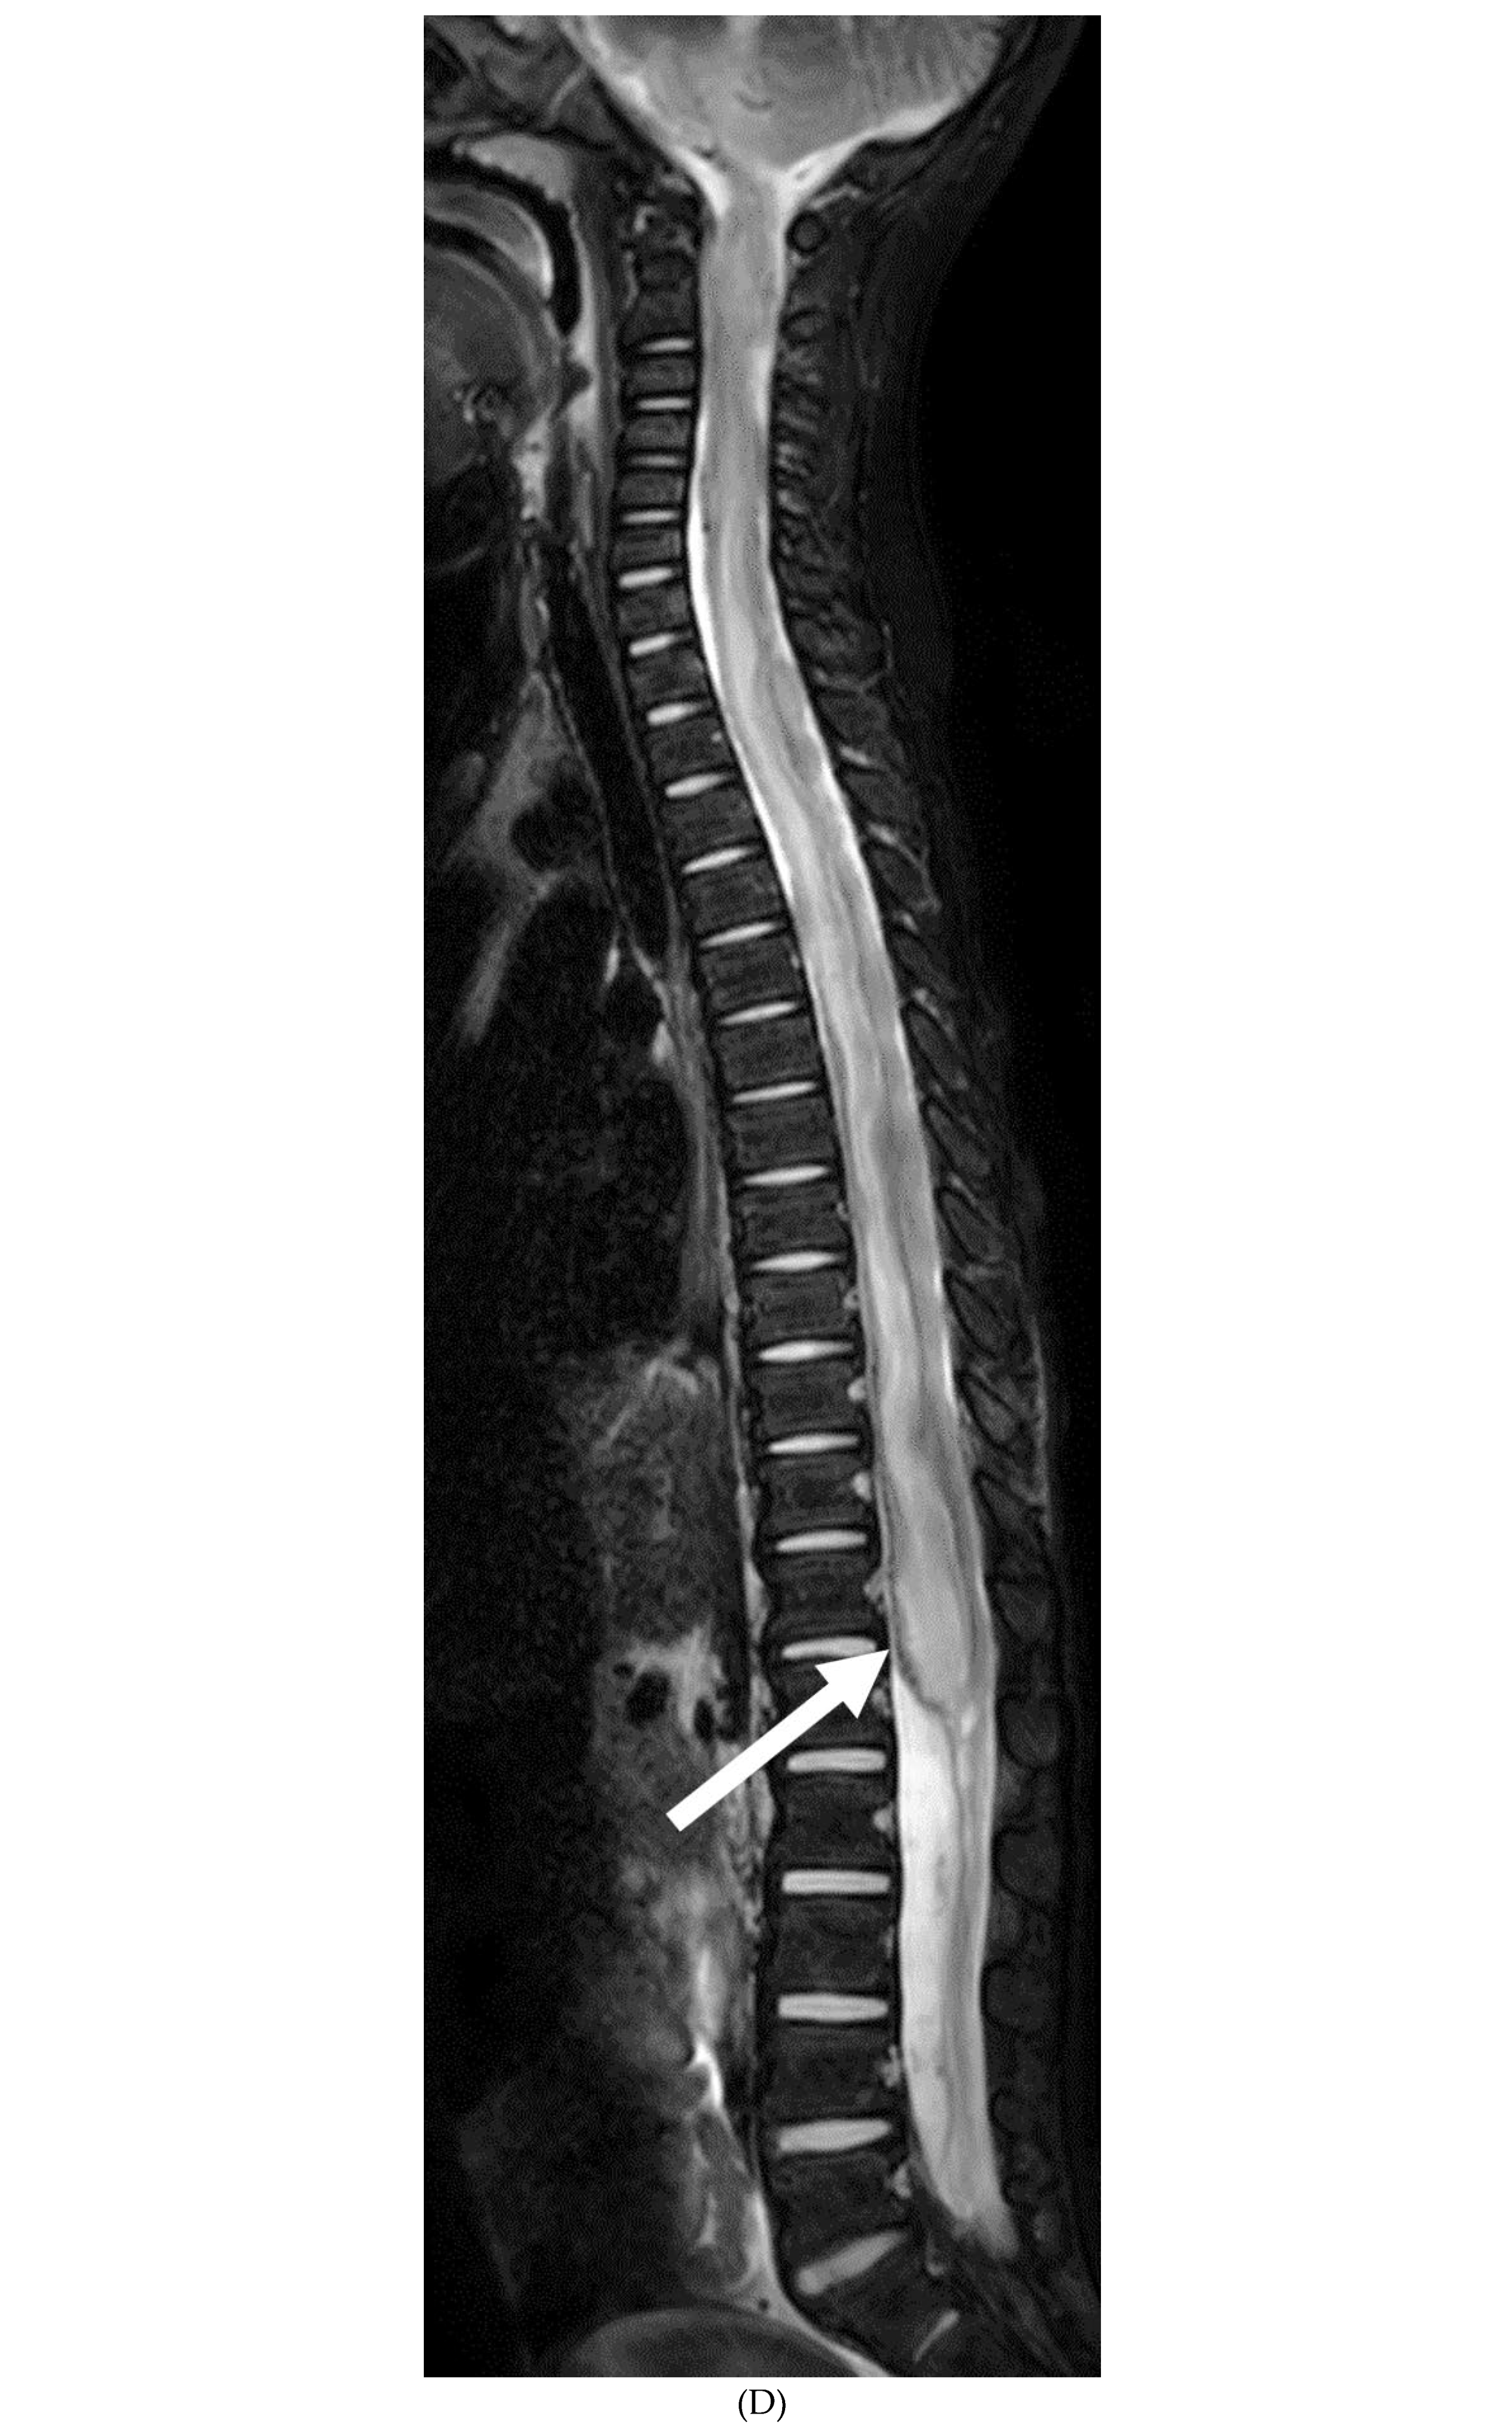

GUILLAIN BARRE SYNDROME

- Alkan O, Yildirim T, Tokmak N, Tan M. Spinal MRI findings of guillain-barré syndrome. J Radiol Case Rep. 2009;3(3):25-8. Epub 2009 Mar 1. PMID: 22470650; PMCID: PMC3303301. [CrossRef]

- Zuccoli G, Panigrahy A, Bailey A, Fitz C. Redefining the Guillain-Barré spectrum in children: neuroimaging findings of cranial nerve involvement. AJNR Am J Neuroradiol. 2011 Apr;32(4):639-42. Epub 2011 Feb 3. PMID: 21292802; PMCID: PMC7965877. [CrossRef]

- Yikilmaz A, Doganay S, Gumus H, Per H, Kumandas S, Coskun A. Magnetic resonance imaging of childhood Guillain-Barre syndrome. Childs Nerv Syst. 2010 Aug;26(8):1103-8. Epub 2010 Jun 17. PMID: 20556395. [CrossRef]

- Byun WM, Park WK, Park BH, Ahn SH, Hwang MS, Chang JC. Guillain-Barré syndrome: MR imaging findings of the spine in eight patients. Radiology. 1998 Jul;208(1):137-41. PMID: 9646804. [CrossRef]